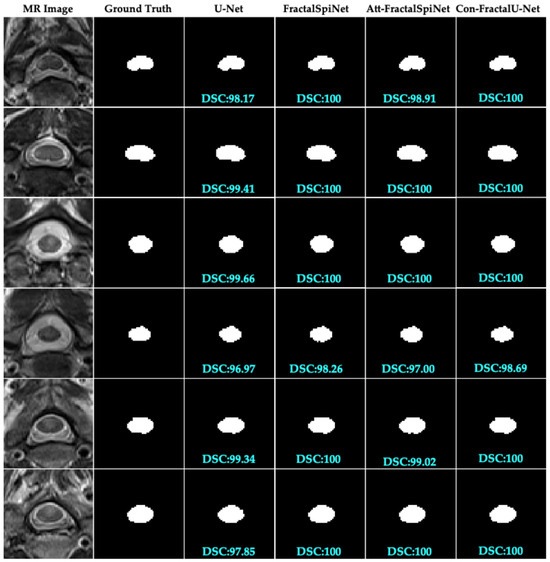

In this study, we compare the performance of the deep learning architectures U-Net, FractalSpiNet, Att-FractalSpiNet, and Con-FractalU-Net for segmentation of CSC MR images. Figure 6 shows the segmentation results for only a part of the test dataset but provides important information about the general trends of the different architectures. In the figures, the segmentation success of each model is evaluated using DSC scores. Con-FractalU-Net demonstrated excellent segmentation performance, reaching 100% for DSC in all test images shown. This shows that the model is able to recognize both spinal cord cross-sectional area (CSA) and MS lesions with very high accuracy and successfully generalize the features learned during training. Similarly, the FractalSpiNet model also achieved a score of 100% within DSC in most cases but was slightly below this value in some images. Although Att-FractalSpiNet includes an attention mechanism to improve segmentation performance, DSC ≈ 98–99% in some test images. This result suggests that while the attention mechanism may be advantageous in certain situations, it may not be sufficient to achieve perfect segmentation in some cases. U-Net was the model with the lowest performance compared to the other architectures. In some images, the DSC value fell below 98% and showed lower accuracy compared to other models, especially in complex boundary regions. This indicates the limitations of the typical U-Net architecture for CSC segmentation, and fractal-based models, which are more advanced structures, appear to be more successful. Together with the full analysis of all test images, Con-FractalU-Net provides the most stable and highly accurate segmentation model. It has been observed that fractal-based networks are more successful than classical CNN-based models and increase segmentation accuracy, especially in medical imaging applications where high precision is required.